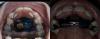

#даняиортодонт

Шикарный результат. Даня еще носит бабочку сейчас?

@yuls_gladkikh, крутой результат!

Спасибо большое за ответ. 🫶🏻